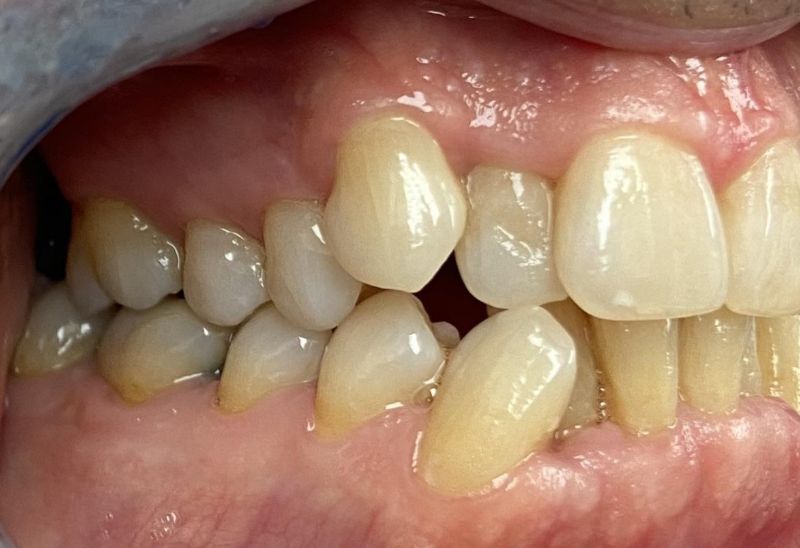

Prima e dopo l'apparecchio invisibile

In questa sezione mostreremo risultati reali ottenuti con l’ortodonzia invisibile a Roma. I cambiamenti riguardano non solo i denti, ma anche l’armonia del viso, la postura orale e l’autostima.